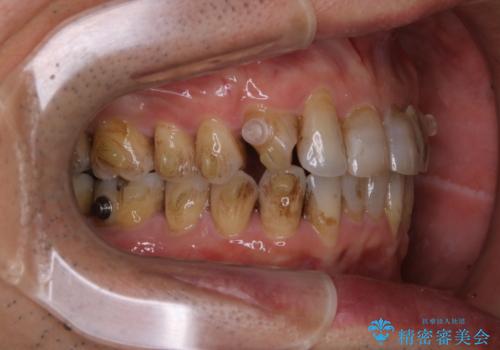

- インビザラインでの矯正中も、コーヒーを頻繁に飲むためステインが気になるとのことでした。PMTC60分コースでなんとかクリーニングを行いました。

インビザライン治療中には、歯の表面にアタッチメント(効率的に歯の移動をするもの)を設定します。そのため歯ブラシでは届きにくい細かい部分などに、歯石や着色がついてしまうことがあります。着色などを放置していると、着色なのか、虫歯なのかの判別もしずらく正確にお口の中の状態を診断できません。